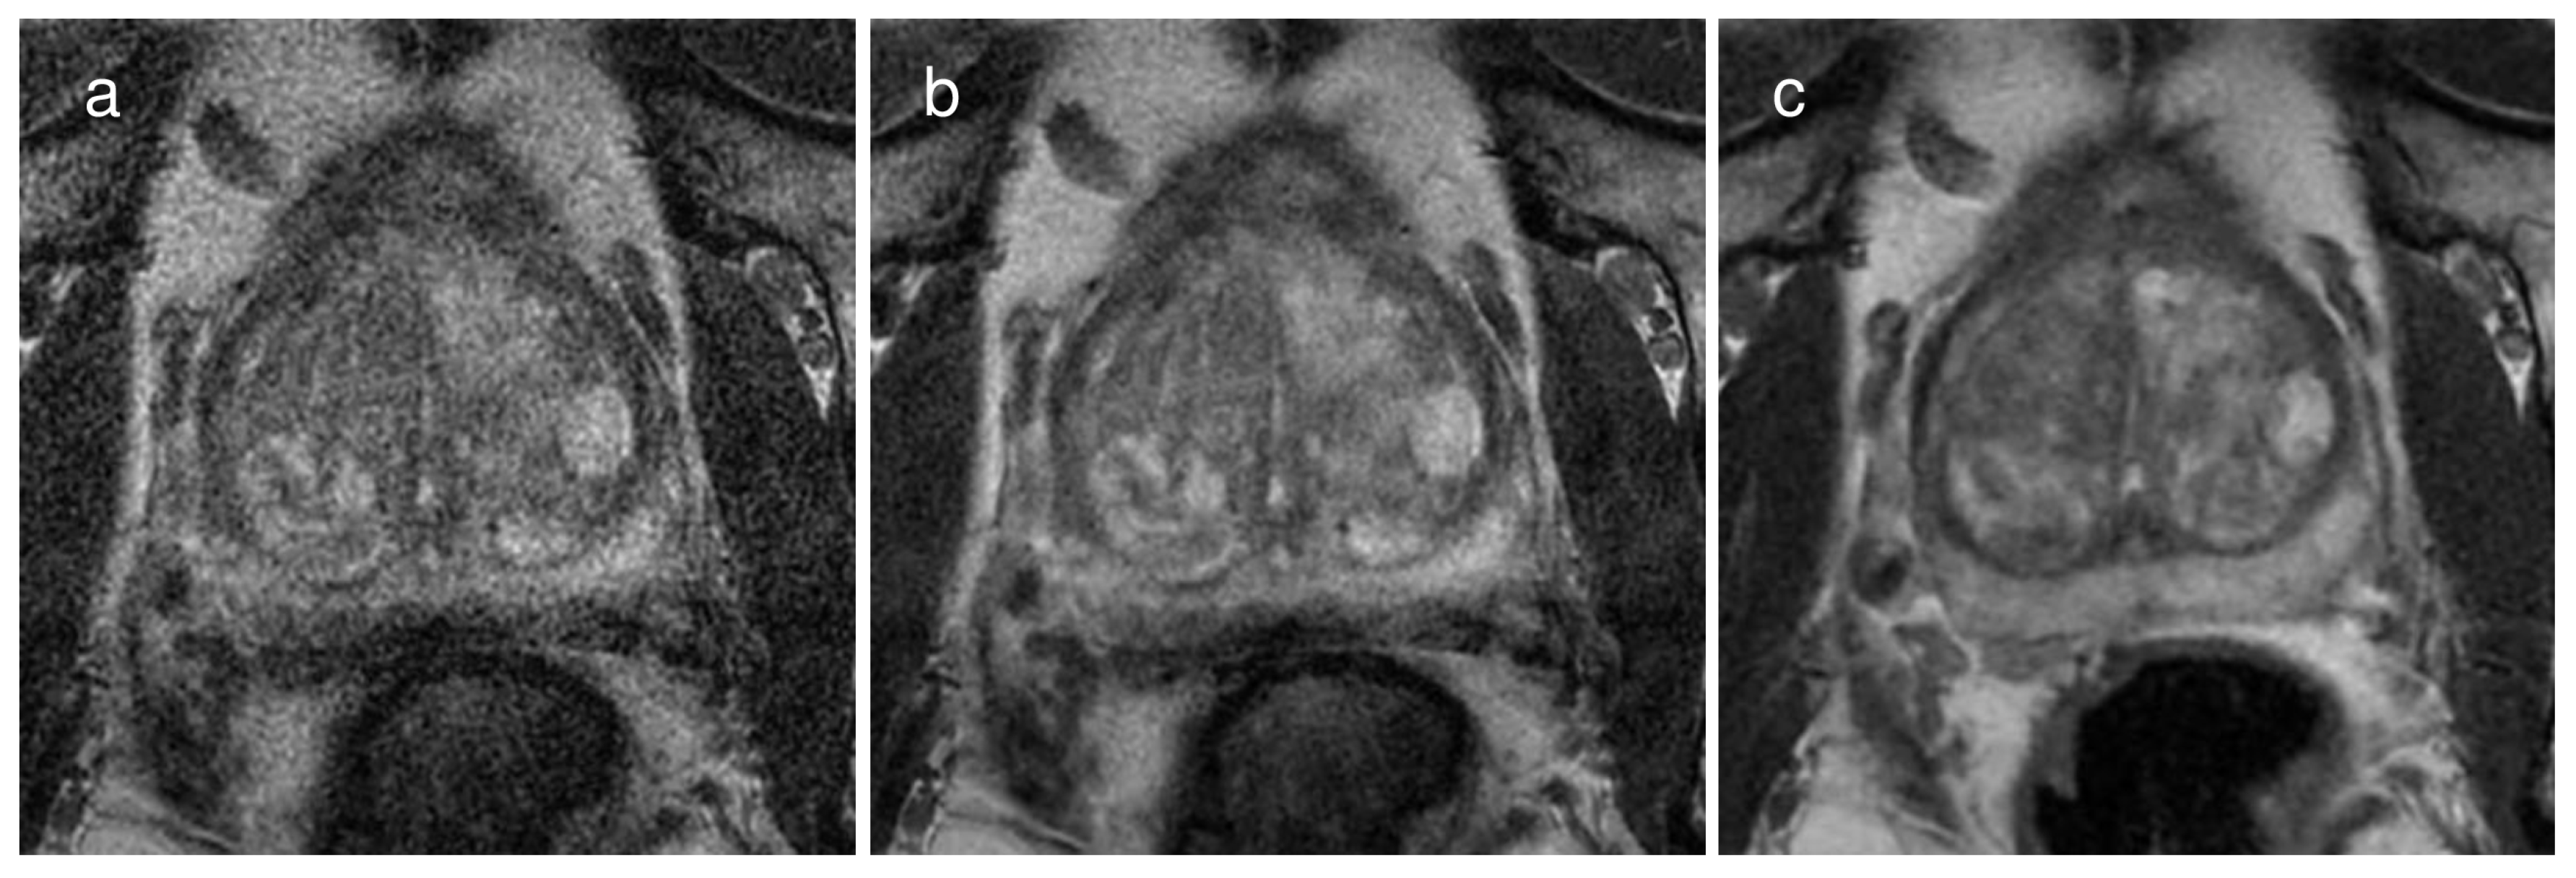

For reviewer 1, the subjective image quality score of T2WIconv (median, 5; interquartile range, 5–5) was greater than T2WIHR with DLR (median, 4; interquartile range, 3–5; p < 0.0001) and T2WIHR without DLR (median, 3; interquartile range, 3–4; p < 0.0001). For reviewer 2, the subjective image quality score of T2WIconv (median, 5; interquartile range, 4–5) was also greater than T2WIHR with DLR (median, 4; interquartile range, 3–4; p < 0.0001) and T2WIHR without DLR (median, 3; interquartile range, 3–4; p < 0.0001). For both reviewers, T2WIHR with DLR had a significantly higher subjective image quality score compared to T2WIHR without DLR (p < 0.0001). Representative images are presented in Figure 3.

Figure 3.

A representative case of a 67-year-old man with a Gleason score of 6 demonstrating the image quality of each image dataset on (a) a 2 mm thin-slice T2WI without deep learning reconstruction (DLR), (b) the same T2WI with DLR, and (c) conventional T2WI with 3 mm slice thickness. The subjective image quality score was the best on conventional T2WI, followed by the thin-slice T2WI with DLR and the same T2WI without DLR. Specifically, the scores were 5, 4, and 3, respectively, for reviewer 1 and 4, 3, and 2, respectively, for reviewer 2.